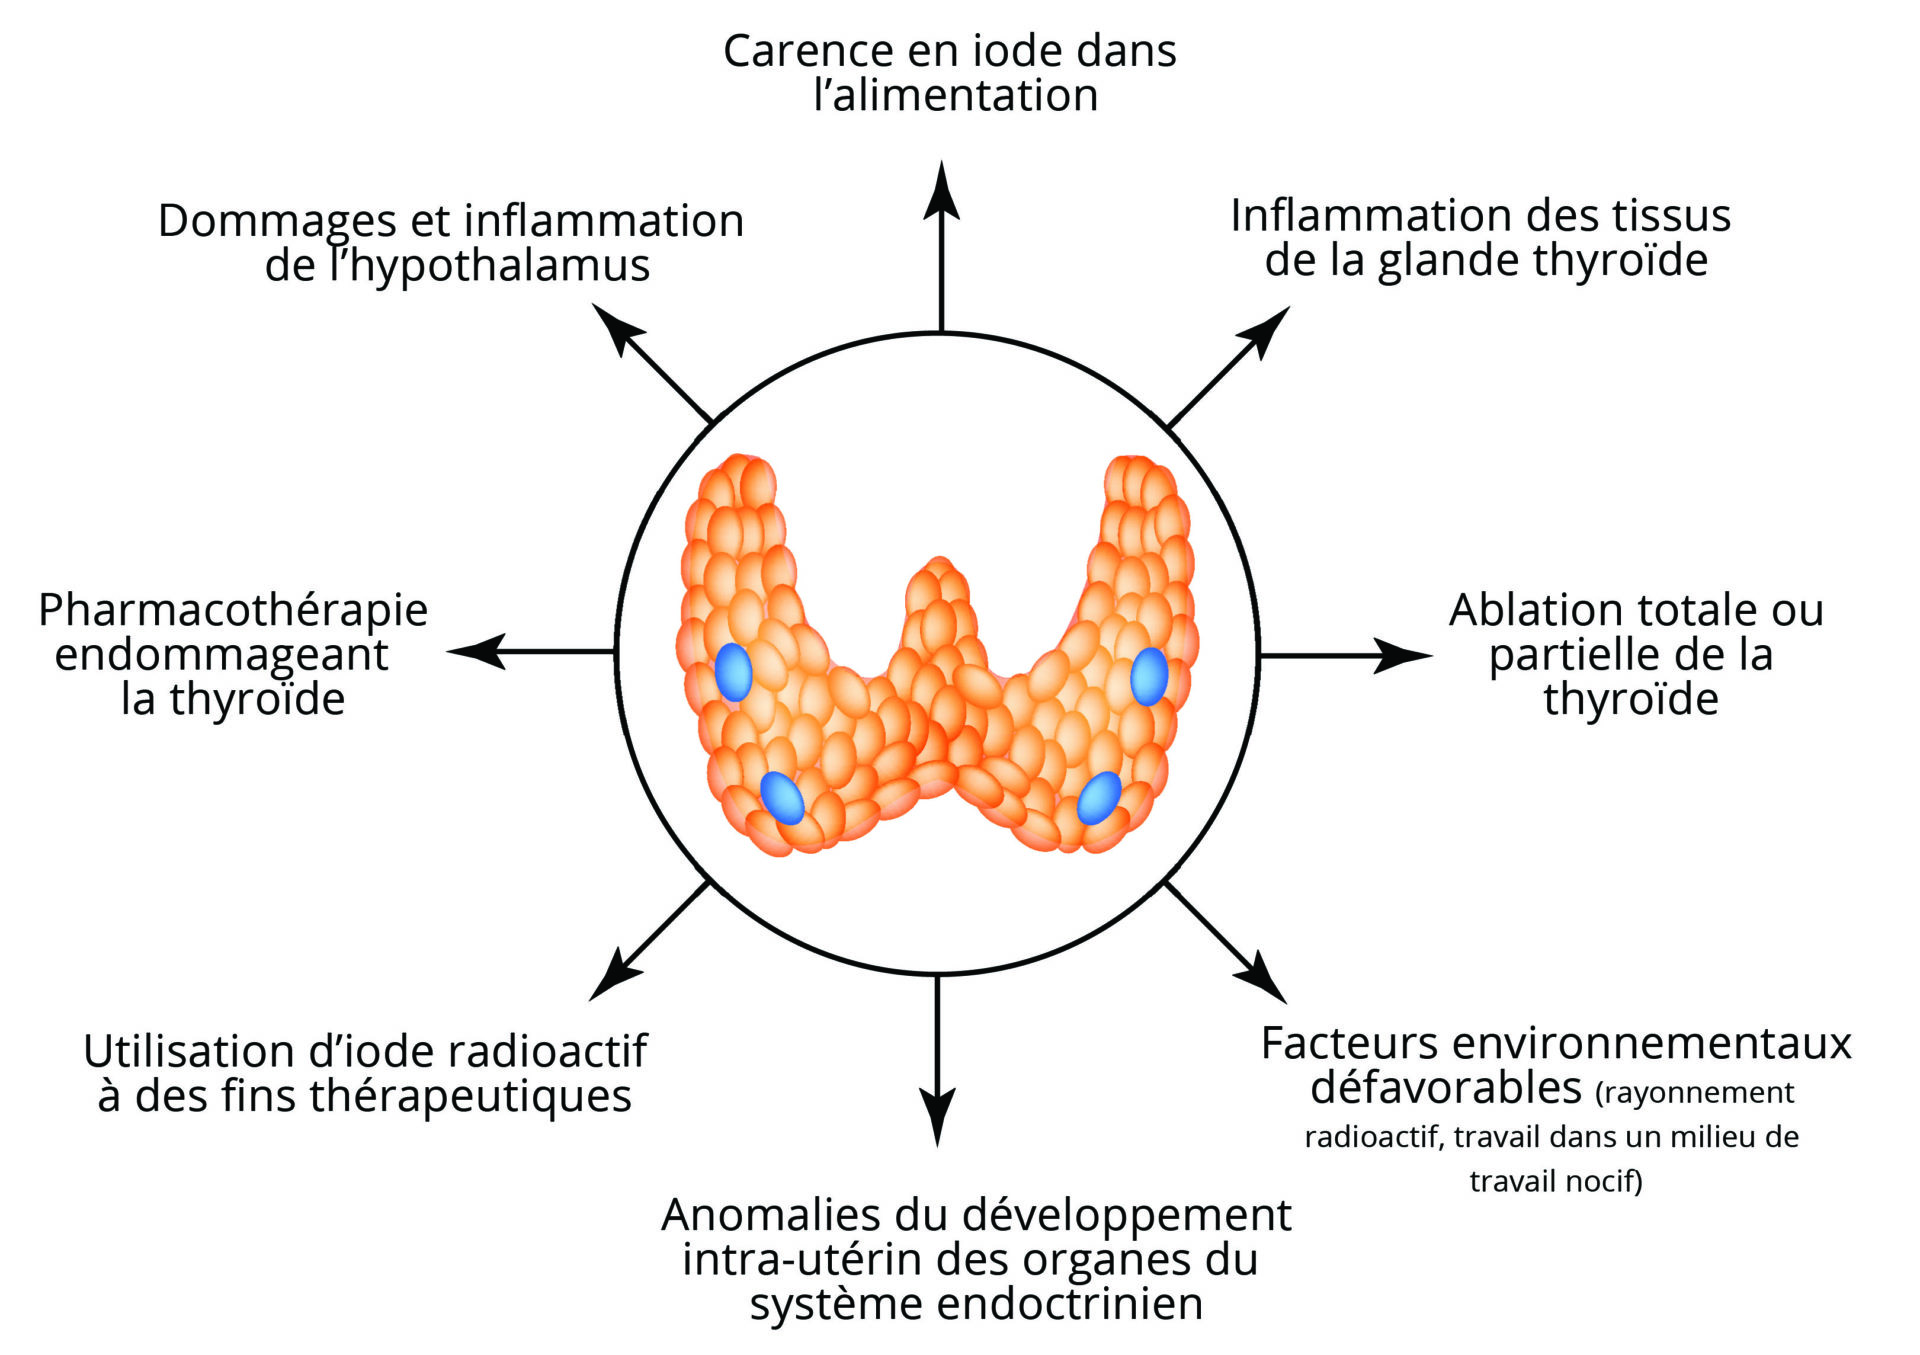

Problèmes de thyroïde : 10 causes auxquelles on ne pense pas